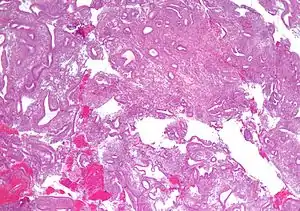

![]() Мікрографія показує просту гіперплазію ендометрія, за якої зберігається співвідношення залоза-строма, але залози мають неправильну форму та/або розширені. Ендоментріальна біопсія Мікрографія показує просту гіперплазію ендометрія, за якої зберігається співвідношення залоза-строма, але залози мають неправильну форму та/або розширені. Ендоментріальна біопсія | |

Залозиста і залозисто-кістозна гіперплазії майже ідентичні, вони розрізняються тільки ступенем вираженості. При залозисто-кістозній формі спостерігаються розширення кістозно-змінених залоз, а при залозистій формі кіст немає. Форма атипової гіперплазії ендометрія характеризується залозами, що розрослися.